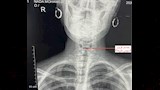

واستقبل قسم الاستقبال والطوارئ بالمستشفى المريضة وهي تعاني من آلام شديدة في الرقبة وصعوبة حادة في التنفس، وعلى الفور تم إجراء الفحوصات والأشعة اللازمة التي أكدت استقرار الدبوس في منطقة دقيقة بمدخل مجرى التنفس، ما شكّل خطورة على حياتها.